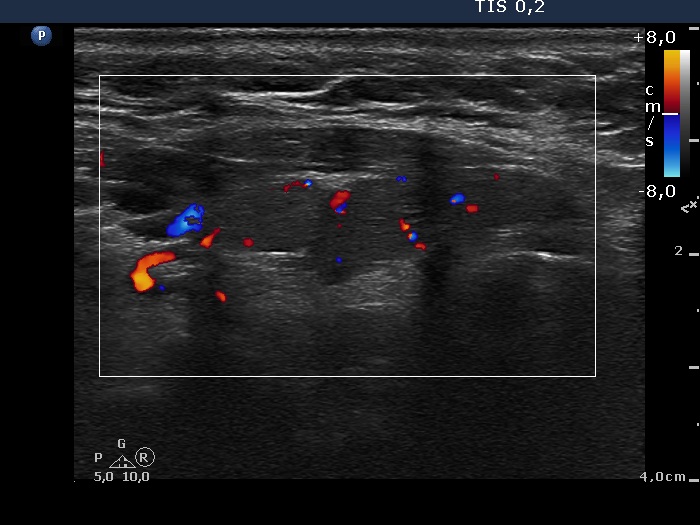

Graves' disease - case 1115

Five years after the surgery (ultrasonographic picture 7)

Left lobe, longitudinal scan, color Doppler mode.